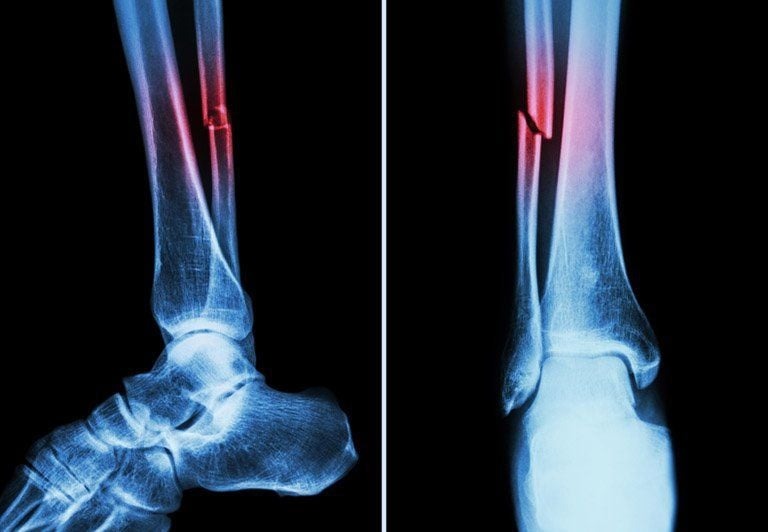

Gãy 1/3 dưới xương mác là một chấn thương thường gặp trong các tai nạn thể thao hoặc tai nạn giao thông. Mặc dù xương mác không phải là xương chính trong việc chịu lực của chân, nhưng nếu không được điều trị đúng cách, có thể dẫn đến các biến chứng không mong muốn. Vậy gãy 1/3 dưới xương mác có nguy hiểm không?

Gãy 1/3 dưới xương mác, nếu không kèm theo các biến chứng như gãy lệch hoặc ảnh hưởng đến các cấu trúc xung quanh, thường không gây nguy hiểm nghiêm trọng và có thể tự lành mà không cần phẫu thuật. Thời gian hồi phục của xương là khoảng 6 - 8 tuần, và mặc dù xương sẽ liền, quá trình phục hồi hoàn toàn trên phim X-quang có thể kéo dài đến 6 tháng. Tuy nhiên, trong suốt thời gian này, việc bảo vệ xương bằng nẹp và tránh va chạm, chấn thương là rất quan trọng.

Xương mác có khả năng tự lành trong thời gian từ 6 - 8 tuần, nếu người bệnh thực hiện đúng các chỉ dẫn và bảo vệ vùng bị thương. Tuy nhiên, phải lưu ý rằng, dù xương có thể lành và hồi phục chức năng, trên phim X-quang, hình ảnh lành xương hoàn toàn sẽ chỉ được thể hiện rõ sau khoảng 6 tháng. Điều này là do quá trình hồi phục và tái tạo xương cần thời gian để vững chắc và hoàn thiện.